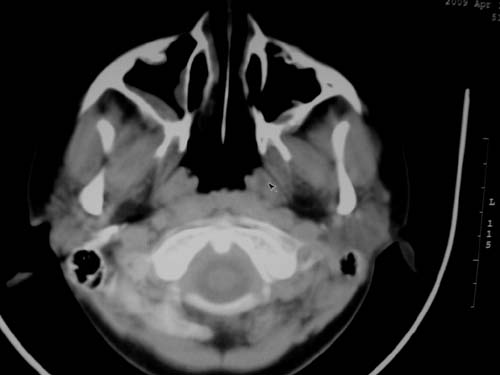

标题: CT19740:女,12岁,鼻塞,流黄鼻涕。 [打印本页]

标题: CT19740:女,12岁,鼻塞,流黄鼻涕。

双侧上颌窦炎,增殖腺肥大。

1)双侧上颌窦炎。2)鼻咽腺样体肥大。